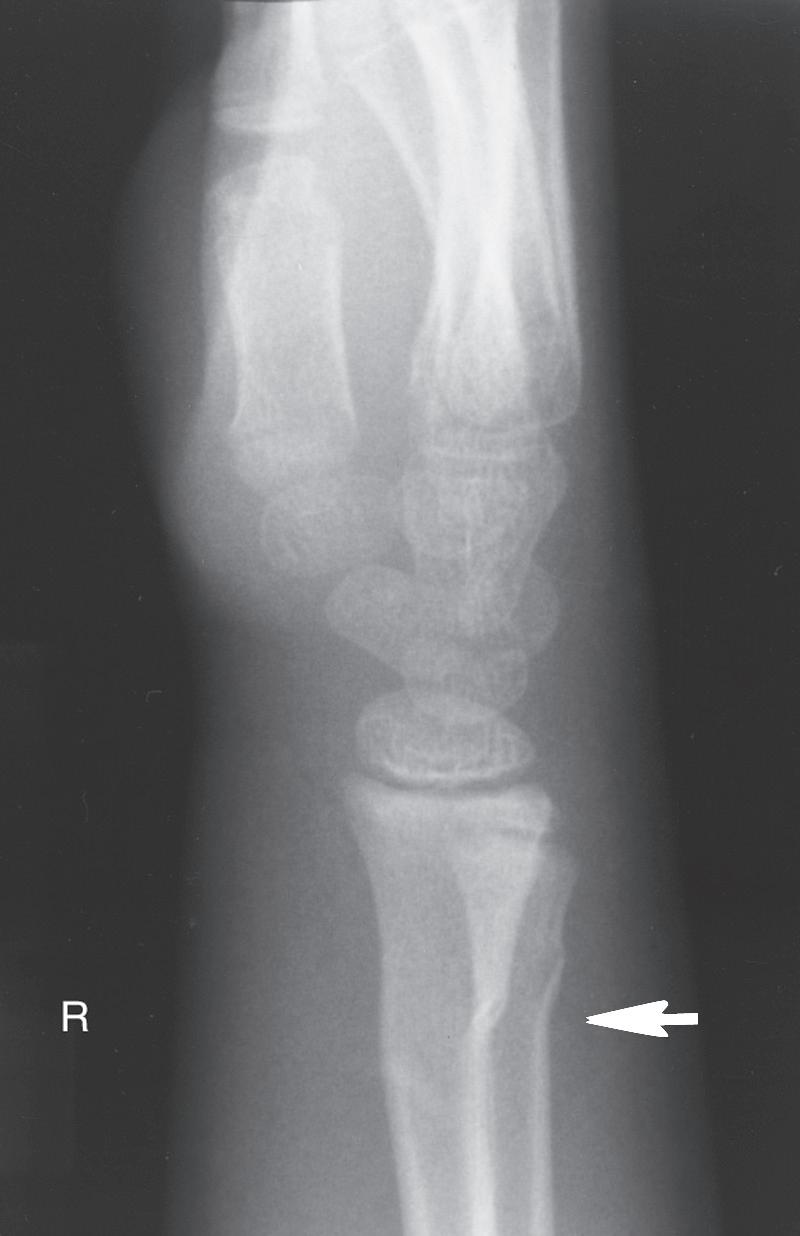

In radiographs of bones that were fractured several weeks to months previously, transverse lines may be seen in the metaphyseal region. These lines are usually referred to as Harris growth arrest lines, or the transverse lines of Park,60 and are unique to children’s bones after a fracture or injury. These transversely oriented trabeculae occur in bones that are normally growing rapidly (e.g., femur or tibia) and in those in which the trabeculae are predominantly longitudinally oriented (Fig. 1.3). When growth deceleration occurs, as happens immediately after a fracture of an extremity, the bone is, in effect, standing still and making transversely oriented trabeculae. The calcified cartilage and bone formed has increased density and is evident radiographically after further growth. Arrest lines should parallel the physeal contour if the physis is growing normally. After a fracture, these lines are typically visible 6 to 12 weeks after injury and can provide the orthopedist with the ability to assess and predict abnormal growth.60 A specific effort should be made to look for these arrest lines during radiographic evaluation of childhood fractures, especially those involving the physes, because lines that do not parallel the physis indicate an area of physeal damage or an osseous bridge.60,61 Arrest lines that do not parallel the physis point to an area of abnormal physeal growth.

The physes that grow more rapidly (e.g., the distal end of the femur or the proximal end of the tibia) have arrest lines farthest from the physis. In the metaphyseal areas of bones, where the slowest growth occurs, transverse trabeculae may be difficult to see radiographically or may not form at all.

Fig. 1.3 Anteroposterior (A) and lateral (B) radiographs of the knee of a 12-year-old child 6 months after a femoral shaft fracture. Arrest lines parallel to the physis can be seen in the metaphyseal area of the distal end of the femur and proximal tibia (arrows). The temporary depression of growth at the time of injury results in more horizontal trabeculae being laid down, thereby increasing the density of bone at that level.